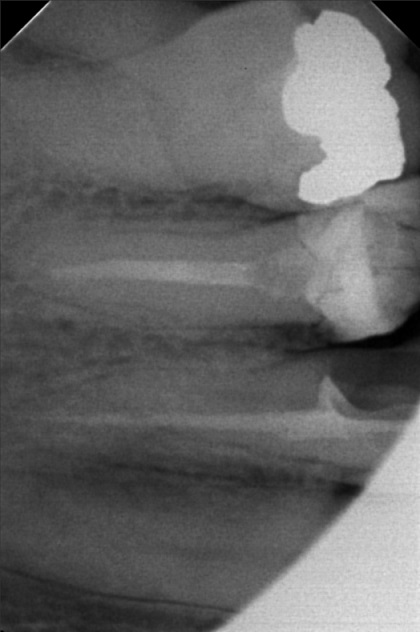

Edit Record Check our patient data records. Add patient information Patient Info Profile picture Last Name First Name Middle Name Birthdate Age Street Barangay City Country Zip Code Contact number Email Procedure > #25 buil-up w/fiber pero > 20mm obturation > xray > icf 09/03/22- open canal/ ML canal Eugenol/ Tf 9/10/10- MB #25 20mm, ML #30 20mm/ Camphenol, TF File sylvia_mariano.jpg File 2 sylvia_mariano_2.jpg File 3 sylvia_mariano_3.jpg File 4 sylvia_mariano_4.jpg File 5 File 6 File 7 File 8 File 9 File 10 File 11 File 12 File 13 File 14 File 15 File 16 File 17 File 18 File 19 File 20 Retain Record Retain Record Yes No Save Your Changes